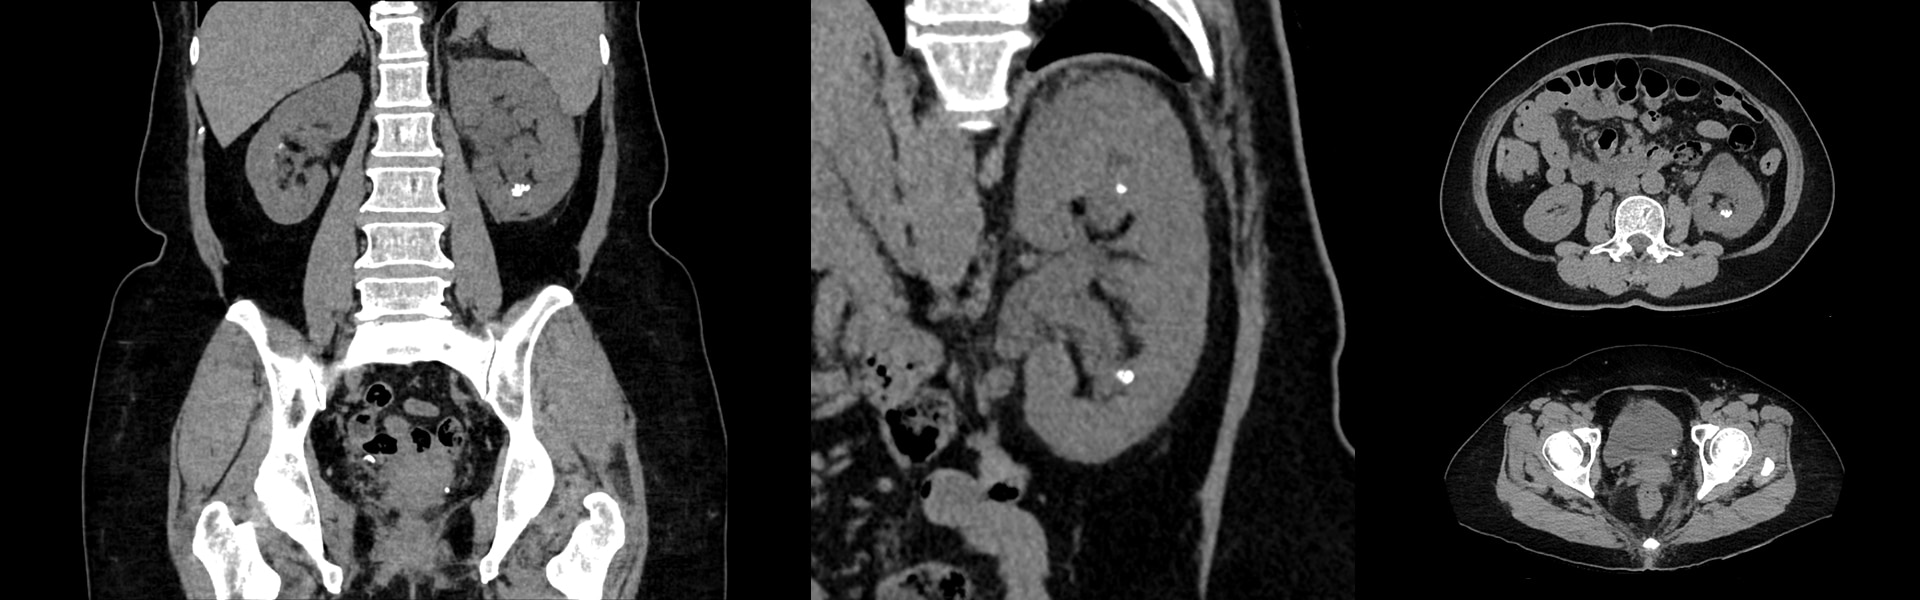

Клинические изображения

Множественные мелкие очаги на ногах и по всей шее

Множественные мелкие очаги накопления на ногах и по всей шее

Размер очага правого уха на КТ 3,5 мм. Опухоль на бедре с разрушением кости

Замер шейного отдела справа – 6 мм